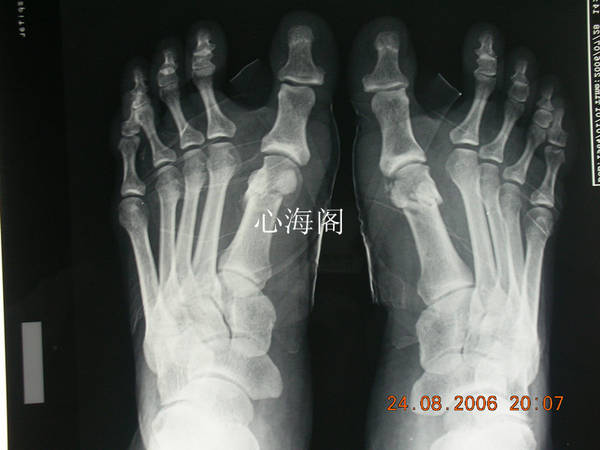

患者,女,56岁,双足拇外翻行微创截骨矫形术。

放松一下,几年前的作品,微创做的,不缝针。不打石膏。

微创主要用磨钻。

1、分别在第一跖骨头内外两侧切2个1cm切口,内侧截骨处开1个cm切口,直达跖骨。

1、先磨去第1跖骨向内的骨突。

2、行第1跖骨截骨,注意勿损失籽骨,复位,冲洗。

3、外侧行关节囊松解术,钝性分离,注意不要把打关节囊完全打开。

4、8字绷带固定,可与第1、2趾间隙处垫少量纱布辅助固定。

5、术后可立即下地,嘱患者全脚掌着地,每周回来更换1次绷带即可。